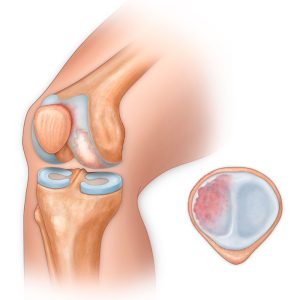

Хондромаляция – это размягчение и разрушение хряща. Заболевание в основном развивается в коленном суставе (хондромаляция надколенника). Больше всего оно характерно для молодых людей, занимающихся спортом (в литературе существует название колено бегуна). Патология довольно распространенная среди спортсменов. Опасность данного процесса состоит в том, что если заболевание не диагностировать на ранних этапах и не провести лечение, развивается остеоартроз коленного сустава.

В зависимость от степени разрушения выделяют:

• Размягчение хряща и отек;

• Трещины и сколы хряща не более 1см;

• Разрушение более 1см;

• Эрозия до кости и глубже.